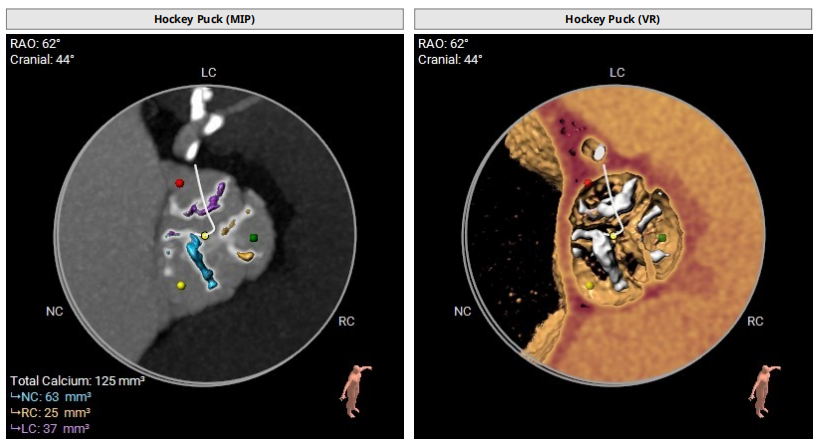

主动脉根部:

三叶瓣,轻度钙化,法式窦结构尚可,左冠开口高度约15.3mm,右冠开口高度约17.1mm,STJ高度约22.6mm、直径约28.8mm,升主动脉未见明显扩张,心脏角度约42°,左室形态大小可,左冠切线位:LAO40° CRA9°,右窦居中位:LAO34° CRA3°,左右重叠位:LOA4° CAU23°。

主动脉弓降部走行欠佳,弓顶部可见钙化,术中操作需谨慎,主动脉弓部三根毛开口未见明显狭窄征象、未见发育异常,胸主动脉、腹主动脉走行较平直,可见多发钙化,类瓷化主动脉,管腔未见明显狭窄征象,双侧髂动脉-股动脉走行稍迂曲,可见多发钙化,部分呈半环形、马蹄形、环形分布,管腔未见明显狭窄征象,若尝试股动脉入路,考虑血管并发症风险,术中操作需尽量轻柔,注意规避穿刺点附近血管前壁钙化,右侧股动脉穿刺水平管腔直径约7.8mm,右侧股动脉分叉约在股骨头下方。